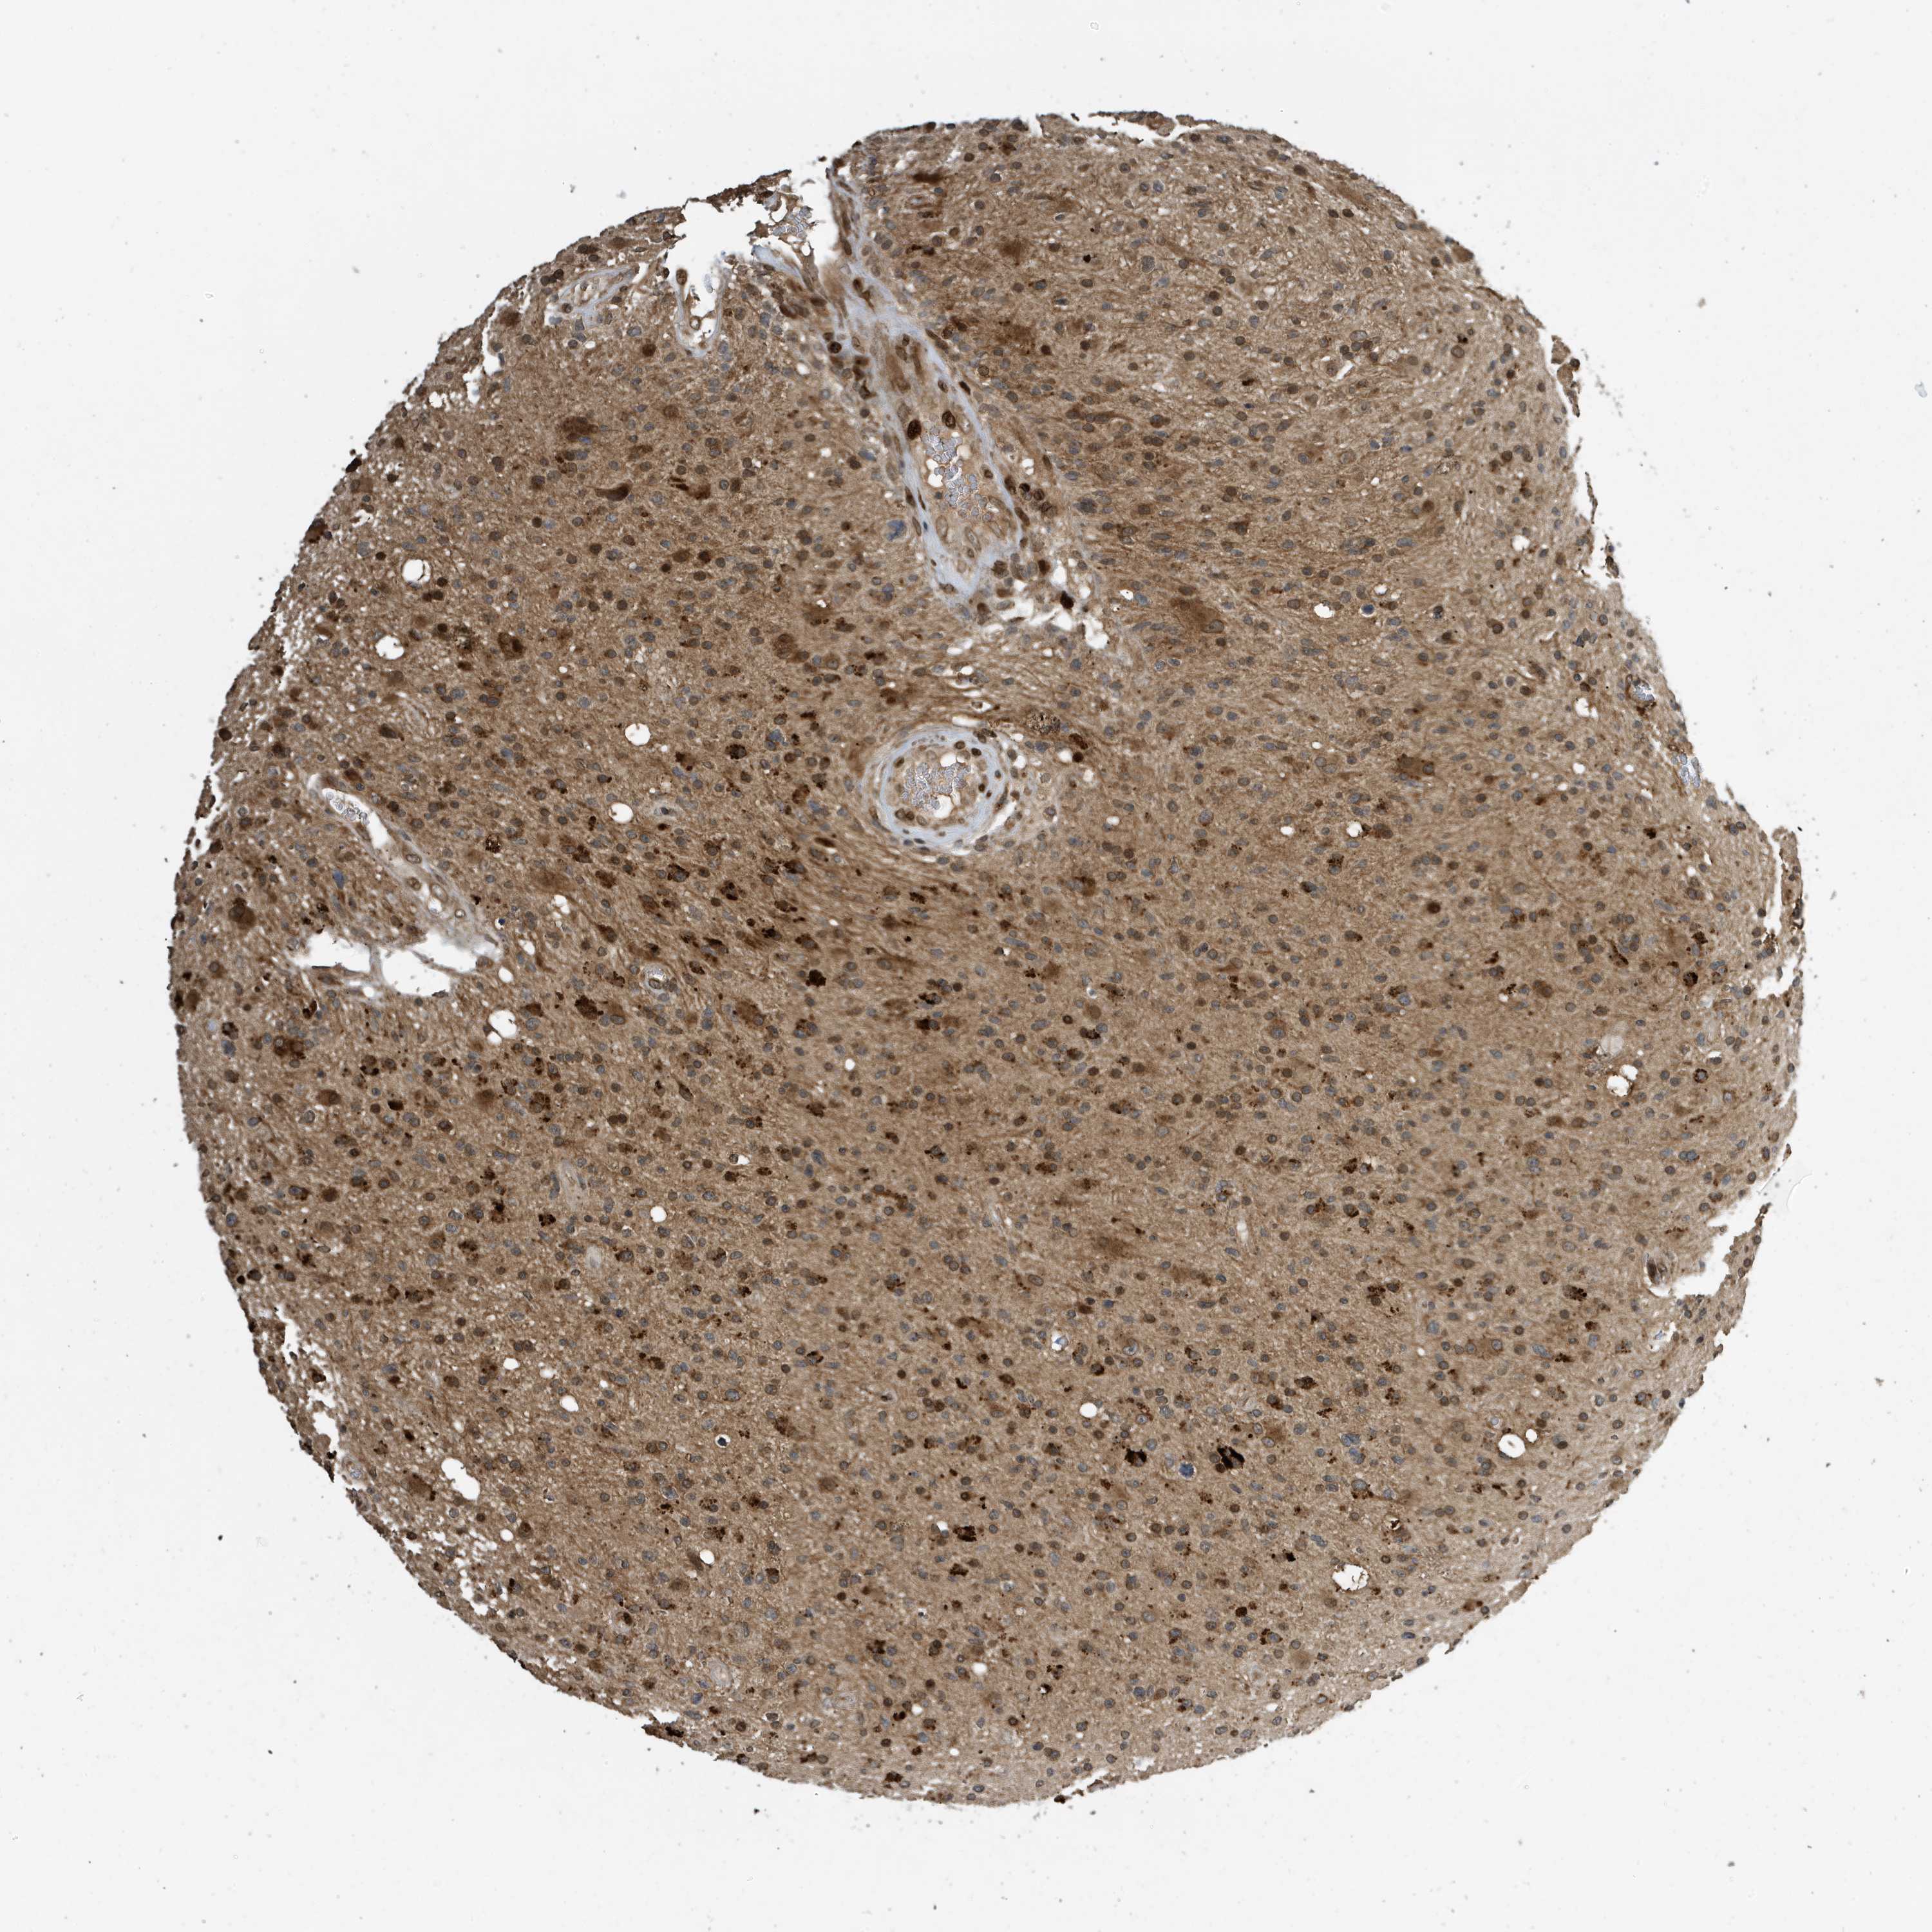

GLIOMA - Protein expressioni

A mouse-over function shows sample information and annotation data. Click on an image to view it in a full screen mode. Samples can be filtered based on level of antibody staining by selecting one or several of the following categories: high, medium, low and not detected. The assay and annotation is described here.

Note that samples used for immunohistochemistry by the Human Protein Atlas do not correspond to samples in the TCGA dataset.

Antibody stainingi

Antibody staining in the annotated cell types in the current human tissue is reported as not detected, low, medium, or high, based on conventional immunohistochemistry profiling in selected tissues. This score is based on the combination of the staining intensity and fraction of stained cells.

Each image is clickable and will lead to virtual microscopy that enables deeper exploration of all samples and also displays staining intensity scores, fraction scores and subcellular localization as well as patient and tissue information for each sample.

Antibody CAB034070

Staining

High

Medium

Low

Not detected

Intensity

Strong

Moderate

Weak

Negative

Quantity

>75%

75%-25%

<25%

None

Location

Nuclear

Cytoplasmic/membranous

Cytoplasmic/membranous,nuclear

Glioma, malignant, High grade

Glioma, malignant, Low grade